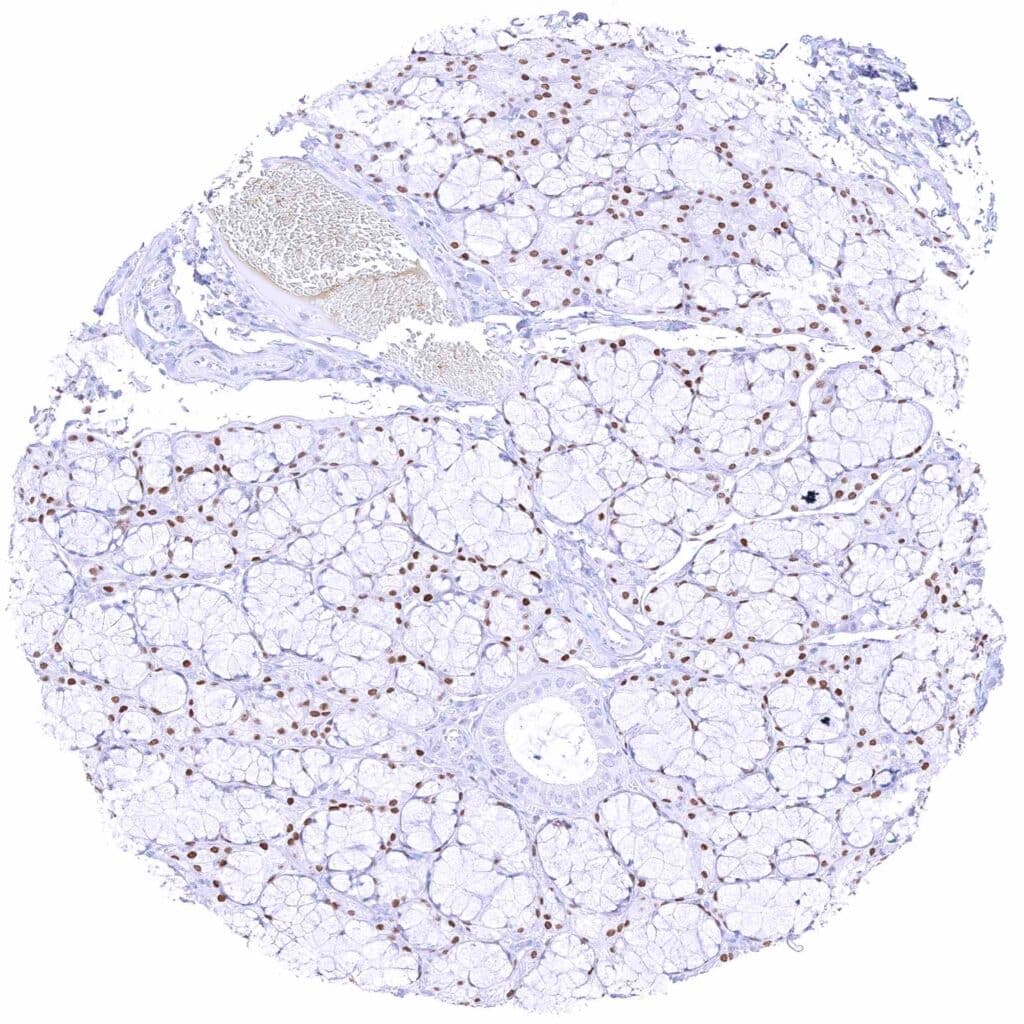

Breast – Moderate to strong GATA3 staining of luminal cells while myoepithelial cells remain GATA3 negative.